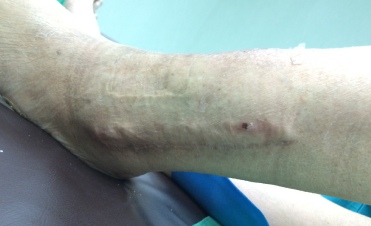

Infeksi pada tulang dapat memberikan banyak variasi gejala, diantaranya berupa timbulnya bisul, nanah, cairan berbau yang keluar terus menerus, adanya lubang yang tidak pernah menutup pada kulit, pembengkakan, warna merah, rasa nyeri, demam, mual dan muntah, dll.

Gambar Contoh Infeksi Tulang